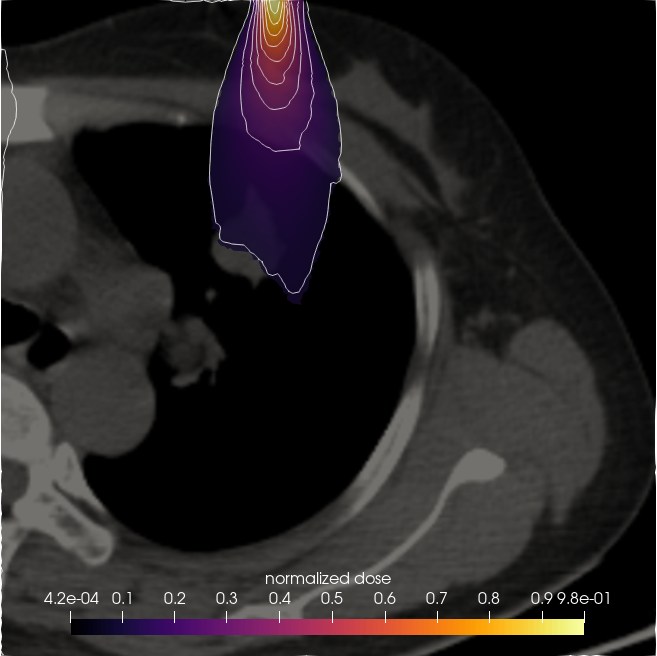

7.3. Beam in 2D patient CT

Having validated the CSD solvers against StarMAP and a Monte Carlo framework in section 7.1, we now examine a realistic 2D CT scan of a lung patient as a proof of concept for the application of our framework to radiation therapy computations. The patient data was retrieved from an open source data set (Li et al., 2020) in The Cancer Imaging Archive (TCIA) (Clark et al., 2013). The patient is irradiated with an electron beam of MeV. We model this beam as the initial condition

where is the beam position within the domain and is the beam direction. The remaining parameters are chosen as . To determine a tissue density for given gray-scale values of the CT image, we set the maximum density, represented by white pixels, to the density of bone . The remaining tissue is scaled such that the minimum pixel value of zero corresponds to a minimal density of . This corresponds approximately to the lower bound of observed lung densities (Kohda and Shigematsu, 1989).

Figure 14 compares the normalized dose for a CSD , and solver. While all methods show similar behaviour and are able to capture the effects of heterogeneities in the patient density, some differences e.g. in the maximum depth of the solution compared to and or the shape of the lowest two isolines can be observed. The cross sections in figure 15 further show that the dose has a lower maximum and higher minimum value than the and to a lesser extent also solutions.